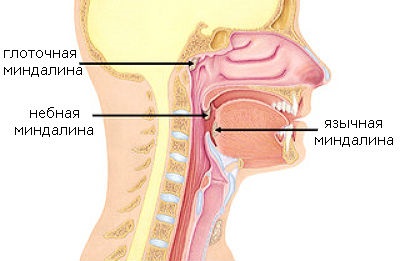

Nasopharyngealis mandula egyike a szervek garat gyűrű, ahol a nyirokszövet társított nyálkahártya-felületek. A fő funkciója az, hogy a helyi immunitás, és létrehozására akadályt mikroorganizmusok belépő levegővel az orron keresztül.

Nasopharyngealis mandulák páros szervek, hogy tegye át a garat szájpadlása. Normális, úgy néznek ki, mint a kis fókák nyálkahártyáját. Szín mandulák körülményektől függ, és jelenléte a gyulladásos folyamat. Normális működés nem különböznek színt a környező szöveteket. Orrpolip találja magát lehetetlen, köszönhetően a nehezen helyét, így a diagnózis nélküli vizsgálatot végző orvos lehetetlen.